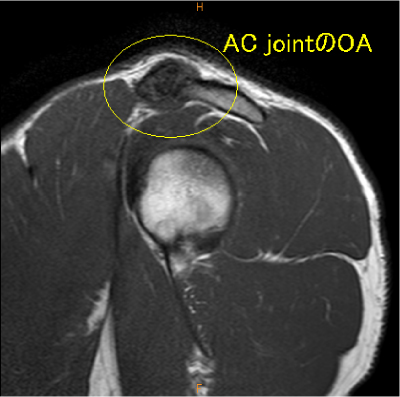

AC jointの変化は慢性の変化で、棘上筋腱の所見がウエイトトレーニング時の外傷による変化であると想像される。

棘上筋腱停止部腱内の剥離, 腫脹著明, AC-jointのOA